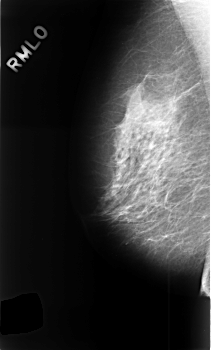

Volume: benign_06 Case: C-0389-1

C_0389_1.RIGHT_MLO

LEFT_MLO LINES 4584 PIXELS_PER_LINE 2744 BITS_PER_PIXEL 12 RESOLUTION 50 OVERLAY

FILE: C_0389_1.LEFT_MLO.OVERLAY

TOTAL_ABNORMALITIES 2

ABNORMALITY 1

LESION_TYPE MASS SHAPE OVAL MARGINS CIRCUMSCRIBED

ASSESSMENT 3

SUBTLETY 5

PATHOLOGY BENIGN

ABNORMALITY 2